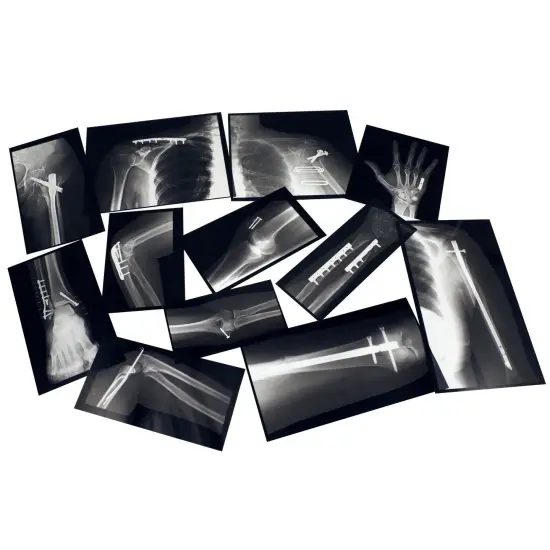

Authentic x-ray images show the hardware (plates, screws, nails, pins and wires) used to fix a broken bone. Fourteen additional images of the fractures, printed on cardstock, correspond to x-rays of the repairs. Use with a light source, such as Roylco's Educational Light Cube, to view details like a doctor would! Great for young learners as well as Secondary Education Science. Includes: 14 x-rays, 14 broken bone images on cardstock up to 7.5 x 11" (19 x 28) and guide. Age 5+ Made in USA

i : Learn about Human Body and how broken bones get fixed

iii : Use with a light source, such as Roylco’s Educational Light Cube, to view details like a doctor would!